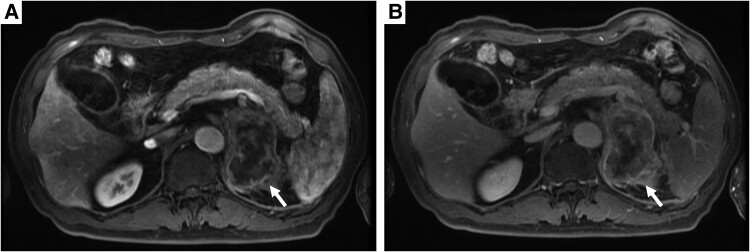

原发性恶性淋巴瘤起源于肾上腺,尤其是起源于t细胞,是非常罕见的。我们报告一例原发性单侧肾上腺间变性大细胞淋巴瘤。一名64岁的日本男性最初表现为疲劳和食欲不振。计算机断层成像显示单侧肾上腺肿块伴多器官侵犯,对肾上腺癌的鉴别提出了挑战。对右外侧股肌转移部位进行活检,免疫组化显示肿瘤细胞CD30和CD56呈阳性,CD3、CD15、CD20、CD43、穿孔素、颗粒酶B、上皮膜抗原和间变性淋巴瘤激酶呈阴性。最终,患者被诊断为原发性单侧肾上腺间变性大细胞淋巴瘤。虽然他对化疗取得了完全缓解,但在完全缓解后4个月,他因胆囊炎和淋巴瘤复发而死亡。

Primary malignant lymphomas originating in the adrenal gland, particularly of T-cell origin, are extremely rare. Here we present the primary unilateral adrenal anaplastic large cell lymphoma case. A 64-year-old Japanese male initially presented with fatigue and appetite loss. Computed tomography imaging revealed a unilateral adrenal mass with multiorgan invasion, posing challenges in differentiation from adrenal carcinoma. A biopsy from the metastatic site in the right lateral vastus muscle was obtained, and immunohistochemistry revealed that tumor cells were positive for CD30 and CD56 and negative for CD3, CD15, CD20, CD43, perforin, granzyme B, epithelial membrane antigen, and anaplastic lymphoma kinase. Ultimately, the patient was diagnosed with primary unilateral adrenal anaplastic large cell lymphoma. Although he achieved complete response to chemotherapy, he died 4 months after complete response due to cholecystitis and lymphoma recurrence.